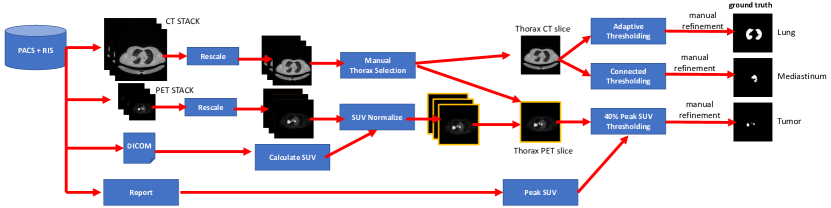

The ground truth was derived from the diagnostic imaging report which detailed the locations of the primary tumor and any involved thoracic lymph nodes. All reports were done by a single, experienced imaging specialist who has read over 80,000 PET and PET-CT scans. We used the report findings to drive a semi-automatic process for ROI labeling. We applied a commonly used adaptive thresholding algorithm [57] to extract the lung ground truth from the CT volume. Similarly, we used connected thresholding to coarsely determine the mediastinum. We extracted the tumor ground truth using 40% peak SUV connected thresholding to detect the ‘hot spots’ identified in the diagnostic reports, which is a general cutoff that is widely used when examining tumors in PET images [58, 59, 60, 61]. Minor manual adjustments were performed to facilitate extraction of the ground truth ROIs (e.g., preventing the left and right lung fields from being joined together with the edge of the mediastinum).

We randomly divided the 50 PET-CT studies into 5 distinct training and test sets for use in a 5-fold cross validation evaluation protocol (see Section II-G). Each training set comprised the slices from 40 studies and its associated test set comprised slices from the 10 other studies. A step-by-step description of our dataset creation process is provided in the Supplementary Materials (Section SIV).